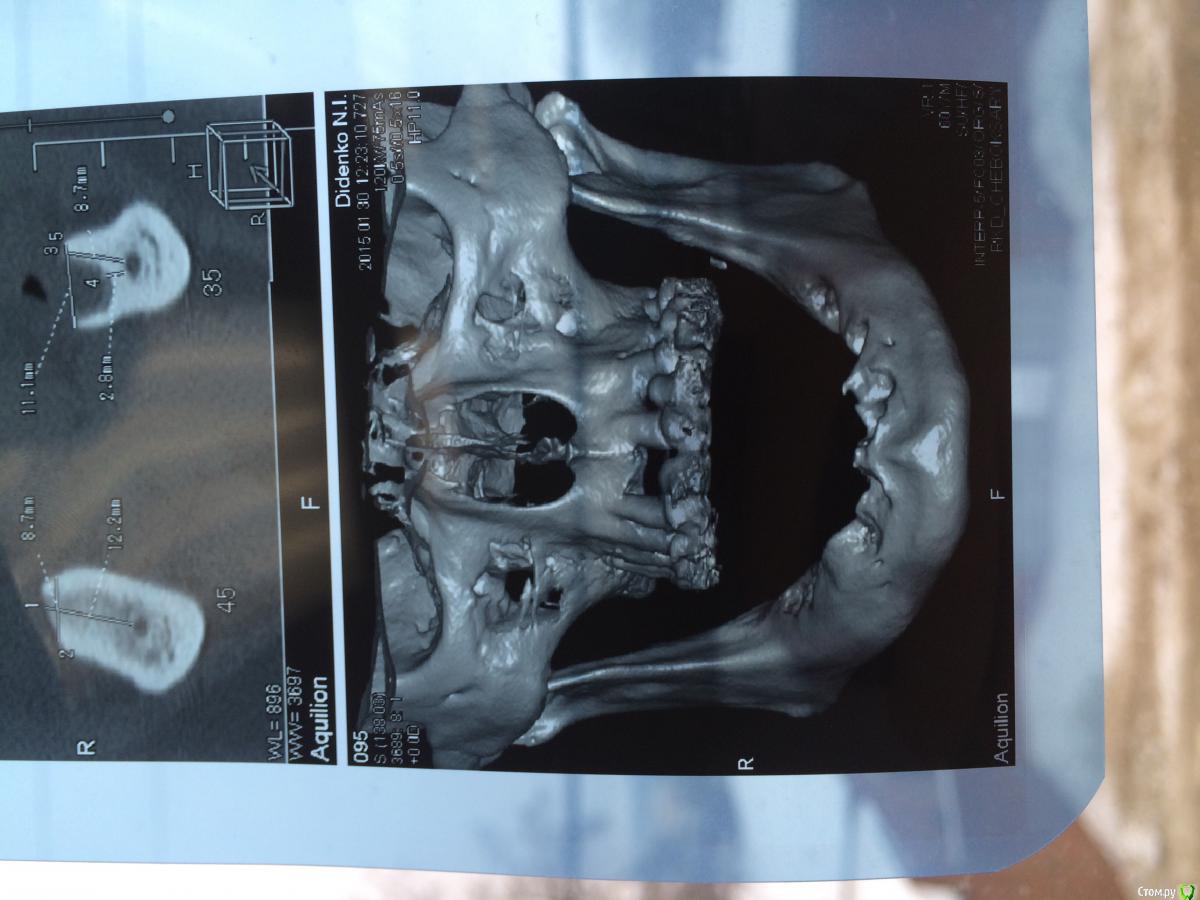

urseva19.05.10 Опубликовано 31 января, 2015 Поделиться Опубликовано 31 января, 2015 Коллеги, в каких позициях на ваш взгляд целесообразнее поставить имплантаты желательно без НКР ( пациент ограничен во времени) что бы в последствии протезироваться съемным протезом на локаторах? На верх не смотрите там все ясно Спасибо! Ссылка на комментарий

faity Опубликовано 4 февраля, 2015 Поделиться Опубликовано 4 февраля, 2015 выровнить гребень и сделать НКР это не одно и тоже. для съемника на локаторах нужен одинаковый уровень винтов и биотип не менее 3-х мм. гребень можно просто выровнять до одинаковой высоты, ямы присыпать придется, десну можно выростить при необходимости.а почему именно локаторы? не хотите балку на 6-ти винтах? условия вроде позволяют Ссылка на комментарий

urseva19.05.10 Опубликовано 4 февраля, 2015 Автор Поделиться Опубликовано 4 февраля, 2015 выровнить гребень и сделать НКР это не одно и тоже. для съемника на локаторах нужен одинаковый уровень винтов и биотип не менее 3-х мм. гребень можно просто выровнять до одинаковой высоты, ямы присыпать придется, десну можно выростить при необходимости.а почему именно локаторы? не хотите балку на 6-ти винтах? условия вроде позволяютСказать честно, может и хочу но с балками ни разу не работал и в лаборатории у нас не делают. Да и экспериментировать с этим пациентом не очень охота. Спасибо за совет. Ссылка на комментарий

red_butler Опубликовано 7 февраля, 2015 Поделиться Опубликовано 7 февраля, 2015 на шести можно и не съемный сделать Ссылка на комментарий

urseva19.05.10 Опубликовано 7 февраля, 2015 Автор Поделиться Опубликовано 7 февраля, 2015 на шести можно и не съемный сделатьПотихоньку задумываюсь об этом. В области каких зубов думаете без нкр получиться? Ссылка на комментарий

АнтонТЛТ Опубликовано 9 февраля, 2015 Поделиться Опубликовано 9 февраля, 2015 Потихоньку задумываюсь об этом. В области каких зубов думаете без нкр получиться?ширина достаточная, так что практически в любом месте можно поставить короткие имплантаты Ссылка на комментарий